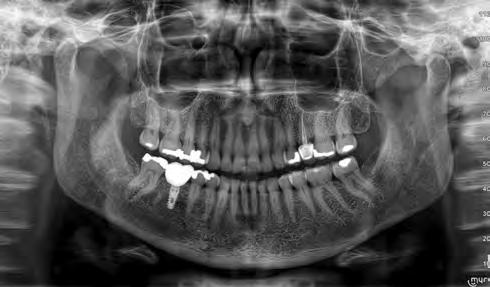

A 77-year-old Caucasian patient presented to the dental clinic after five years without dental care. The clinical findings showed significant bone loss, chronic periodontitis, and loss of some teeth that stabilized the occlusion. The patient reported cold sensitivity in tooth #46, especially when ingesting liquids.

Periapical X-ray confirmed the findings of the clinical examination and root caries was also detected in the distal root of tooth #46, which answered positively to the sensitivity test (Fig.1-2).

The treatment plan began with a focus on returning the patient to adequate periodontal health. In a subsequent session, with improved condition of the periodontium, the restoration of tooth #46 was performed. Under block anesthesia of right inferior alveolar nerve and rubber dam isolation, the amalgam restoration was completely removed and access to the caries cavity obtained (Fig. 3-5). Despite the proximity to the pulp tissue, no exposure occurred, and the class II cavity was fully restored with Biodentine™ (Fig. 6-8).

At two months’ follow-up, no symptoms were reported, no periapical lesion was observed radiographically, and the clinical examination showed normal vitality (Fig. 9-10). Thus, it was decided to perform the definitive restoration, leaving Biodentine™ as the definitive base.